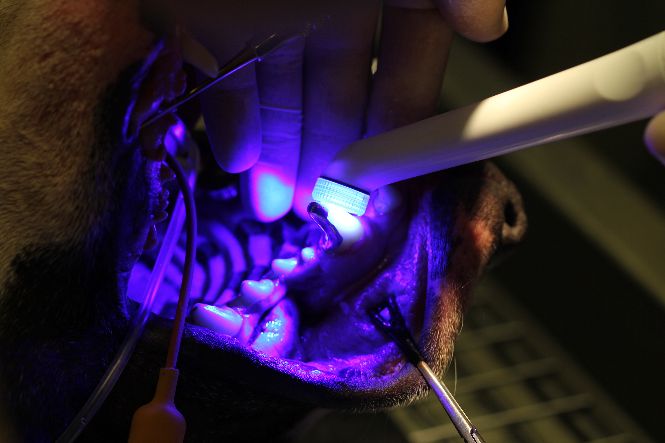

Curing cement with ultra violet light

Close up photograph of fitted crown